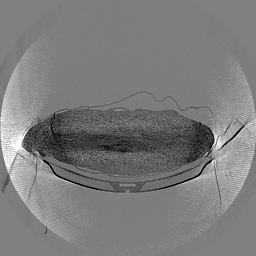

The results for simulated noisy data are shown in Fig. 2. The first and third rows display two representative slices from the test set, and the second and fourth rows present the corresponding error maps. The traditional WCE method suppresses cupping artifacts and recovers some missing anatomical structures but still shows noticeable deviations from the ground truth. Predictions from the four diffusion-based models demonstrate a markedly improved ability to restore anatomical structures. Among them, cDDPM fails to fully reconstruct the patient bed and retains residual noise in its outputs. This noise is attributable to an incomplete reverse denoising process rather than residual Poisson noise, as evidenced in our noise-free experiments (Fig. 5 in the Appendix). PatchDiffusion, diffusionGAN, and I2SB achieve similar visual quality, with I2SB producing the cleanest and most consistent reconstructions.

Quantitative results in Tab. V further confirm I2SB’s superiority over conventional deep learning methods such as FBPConvNet and Pix2pixGAN across RMSE, PSNR, and SSIM. Compared to other diffusion models—including cDDPM, PatchDiffusion, and cLDM—I2SB delivers higher image quality, while diffusionGAN achieves comparable quantitative performance. However, I2SB demonstrates a significant advantage in inference efficiency, as summarized in Tab. IV.